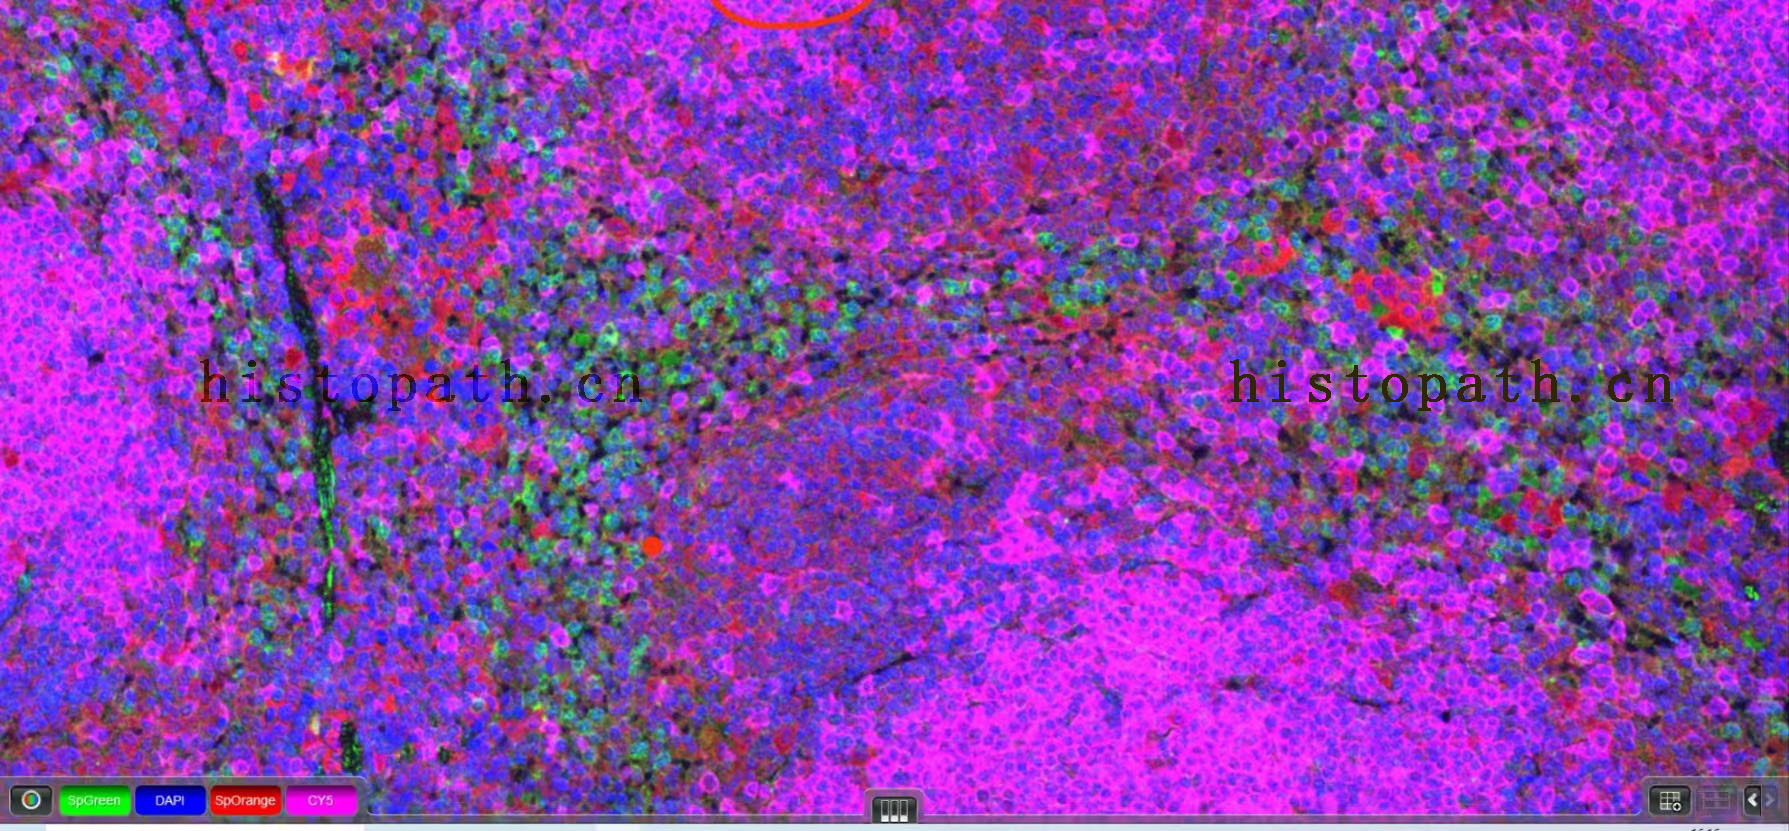

免疫荧光

免疫荧光单标双标多标(三标四标五标六标)

二、免疫荧光(双标)

免疫荧光双重标记即利用抗原抗体特异性结合原理,在同一张切片上两个抗原进行同时标记,从而实现定位,定性,半定量的分析。1、石蜡切片脱蜡至水:依次将切片放入二甲苯Ⅰ15min-二甲苯Ⅱ15min-无水乙醇Ⅰ5min-无水乙醇Ⅱ5min-85%酒精5min-75%酒精5min-蒸馏水洗。

10、镜检拍照:切片置于扫描仪下采集图像。(DAPI紫外激发波长330-380nm,发射波长420nm,发蓝光;FITC激发波长465-495nm,发射波长515-555 nm,发绿光;CY3激发波长510-560,发射波长590nm,发红光. CY5激发波长 608-648nm, 发射波长672-712。 DAPI染出来的细胞核在紫外的激发下为蓝色,阳性表达为相应荧光素标记的红光,绿光 。